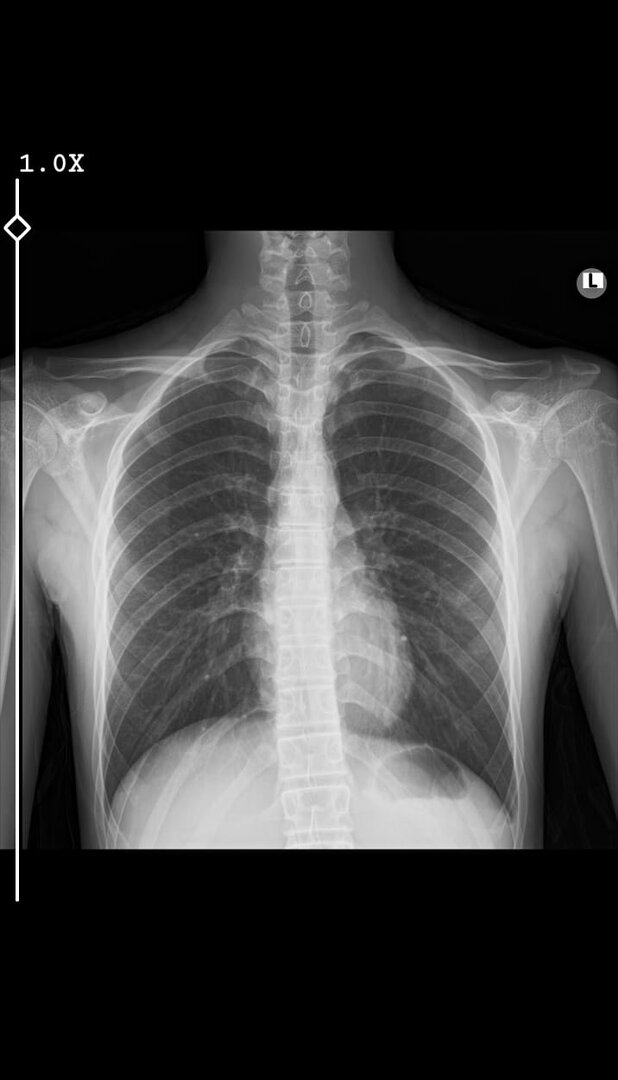

Birkaç ay önce doktor bana skolyoz olduğumu söyledi MSÜ işi benim için bitti 1 derece bile olsa almıyorlarmış. Bende dış alımlarla girmeyi düşünüyorum. Dış alımda sağlıktan elenir miyim?

Kim diyor 1 derece bile olsa almıyorlar? Onun derecesini iyi araştır belli sınırları var. Ayrıca görünürdede pek bir yamukluk yok gibi.

Omurganın A/P planda ayakta çekilen grafilerinde 5 dereceye (5derece dâhil) kadar olan eğrilikler Hava Harp Okulu öğrenci adayları hariç, tüm öğrenciadaylarında sağlam kabul edilir.